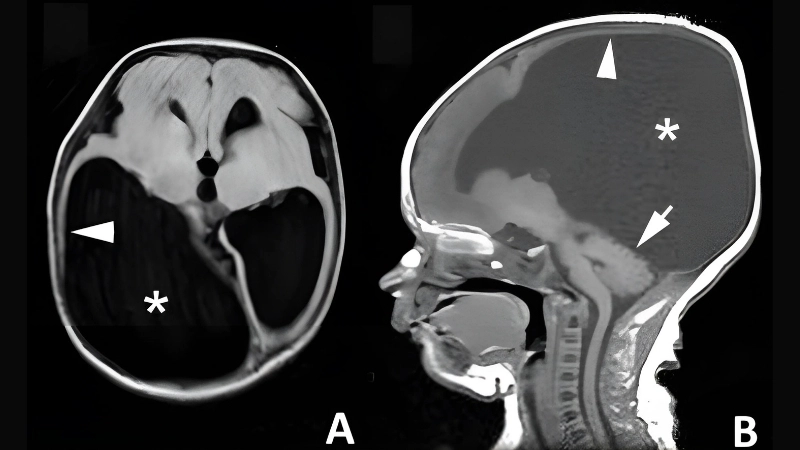

A microscopic view of the LCM virus shows its rodent-transmitted viral particles, highlighting the source and mode of human infection. The virus primarily targets the nervous system, causing inflammation and fever.

LCMV may lead to hydrocephalus in severe infections